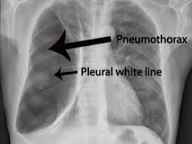

قیمت: 32٬000 تومان - دسته بندی فایل: پاورپوینتپاورپوینت پنوموتوراکس

فروش ویژه پاوزپوینت حرفه ای پنوموتوراکس با تخفیف استثنایی قیمت 49 هزار تومان تعداد اسلاید: 13 اسلاید